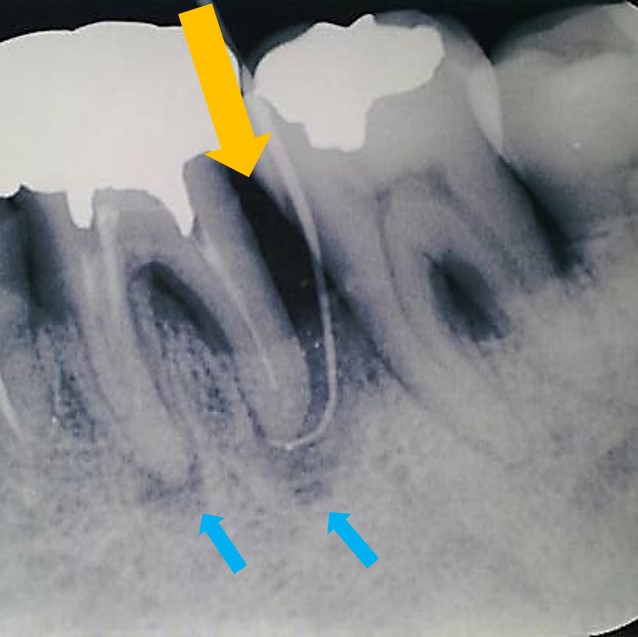

術後が下写真です。

オレンジ矢印の部分に骨再生が認められ、歯周ポケットも9mmから3mmに改善しました。また根尖部透過像(根尖病巣:青矢印)も改善しています。

歯周ポケットからの感染と根管内からの感染が合わせて起こった場合はとても治りにくいのですが、良好に改善したケースといえます。